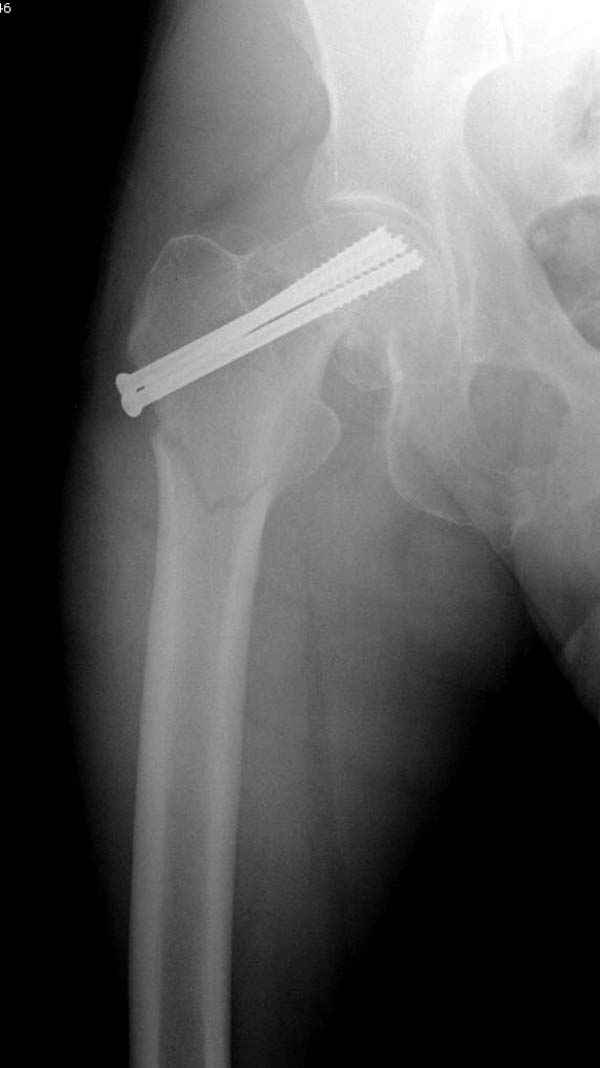

Re: неполный перелом шейки

Профилактику дальнейшего раскола неполного перелома шейки провели тремя канюлированными шурупами.

На второй день после выписки упал дома. Снимки приложены. Коллеги рекомендуют удаление шурупа и вытяжение. Что делать?